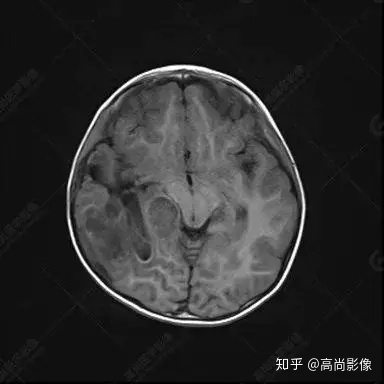

右側(cè)顳葉腫瘤切除術(shù)后(具體不詳):右側(cè)顳部骨質(zhì)不連續(xù)呈術(shù)后改變,右側(cè)顳葉術(shù)區(qū)見片狀長T1長T2信號(hào)影,F(xiàn)LAIR呈低信號(hào);術(shù)區(qū)后方右側(cè)顳枕葉見一巨大占位性病變影,邊界欠清,大小約6.2×5.8×4.3cm(前后×左右×上下),信號(hào)不均勻,T1WI呈等稍低信號(hào)間雜少許高信號(hào),T2WI呈高稍低混雜信號(hào),DWI示部分病灶彌散受限,相應(yīng)ADC圖減低,磁敏感序列見部分呈極低信號(hào),增強(qiáng)掃描可見明顯不均勻強(qiáng)化,鄰近硬腦膜及小腦幕增厚并明顯強(qiáng)化;另延髓右前方及右側(cè)橋小腦角區(qū)見一不規(guī)則形異常信號(hào)影,大小約3.2×1.3×3.7cm(左右×前后×上下),呈長T1稍長T2信號(hào),F(xiàn)LAIR呈等信號(hào),DWI未見受限,增強(qiáng)后明顯均勻強(qiáng)化,鄰近腦膜明顯強(qiáng)化。鄰近腦實(shí)質(zhì)及右側(cè)顳角明顯受壓;左側(cè)大腦半球未見局灶性信號(hào)異常,中線結(jié)構(gòu)稍左移。

右側(cè)顳葉腫瘤切除術(shù)后:現(xiàn)術(shù)區(qū)后方右側(cè)顳枕葉及延髓右前方占位,右側(cè)顳枕部硬腦膜及小腦幕明顯強(qiáng)化,結(jié)合既往影像資料,考慮為胚胎源性惡性腫瘤,如非典型畸胎樣/橫紋肌樣瘤(AT/RT)或原始神經(jīng)外胚層腫瘤(PNET)。